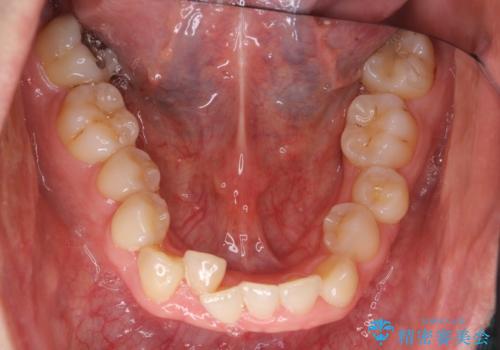

受け口 絶対に顎の手術はしたくない

- 受け口を主訴に来院。

下あごが大きく、顎の手術を含めた矯正をおすすめしましたが、手術は怖いので絶対にしたくないとのことでした。

歯並びのみを治す矯正は難しく、長期にわたる治療になるとご説明しました。

かみしめもあり、骨も固く、歯根も長いためなかなか歯が動かず、患者様も治療する側も忍耐を要する長期戦となりました。